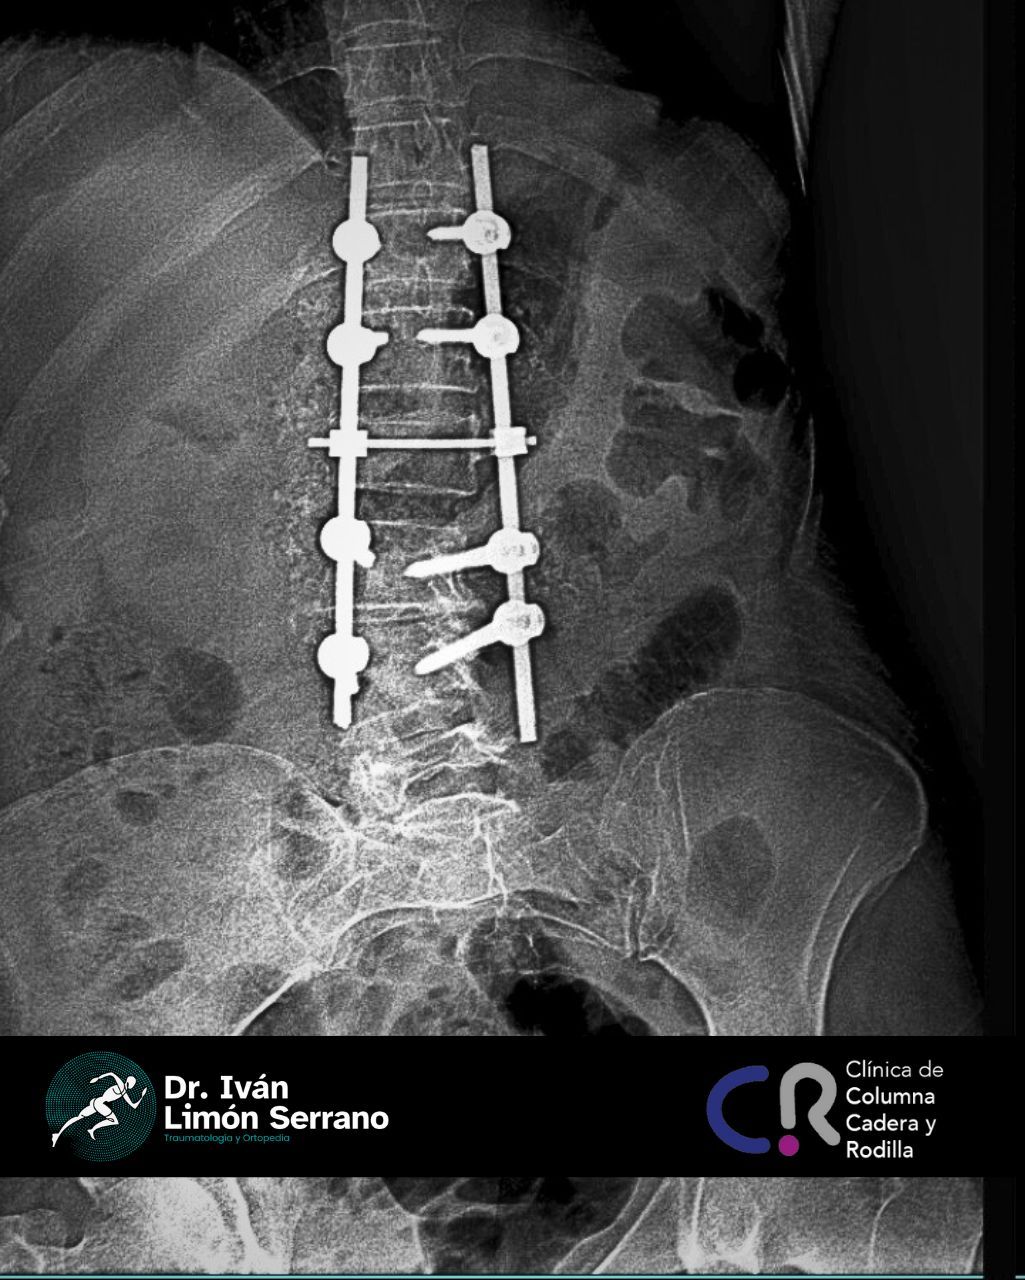

• Cirugía de columna

• Cirugía columna